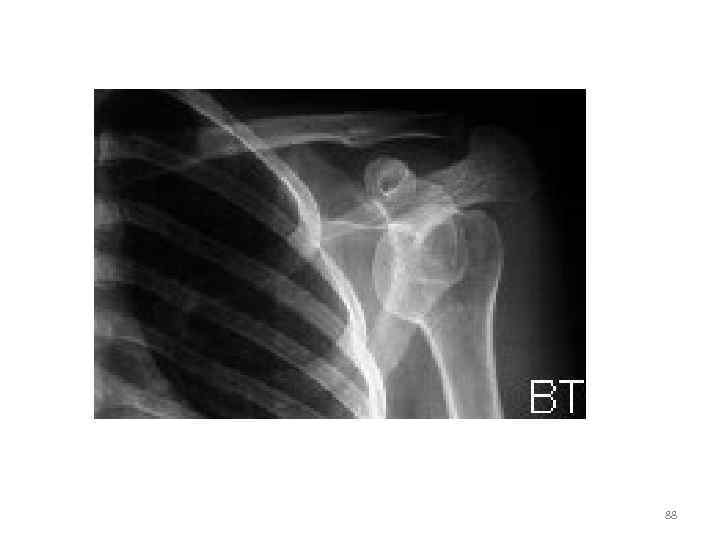

88

• На рентгенограмме области левого плечевого сустава в задней проекции определяется: полный передний вывих в плечевом суставе 89